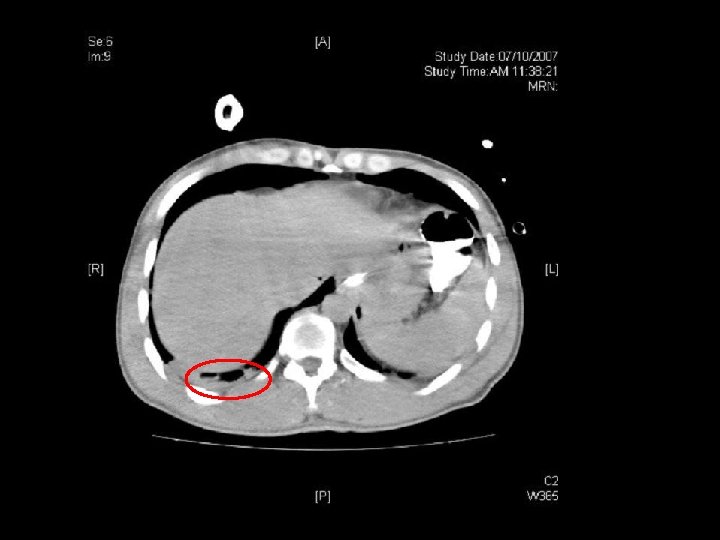

Dx: decompression sickness bilateral chest drain inserted Bilateral myringotomies performed 1 st session of recompression Urgent contrast swallow: no definite leakage in thoracic region

2 nd, 3 rd and 4 th session recompression on D 2, D 3 and D 4 respectively Persistent RUL monoparesis CT brain: hypodensity over L frontaloccipital lobe ? recent infarct MRI brain: acute infarct over L frontoparietal region Dx: deompression illness with pneumothorax, pneumoperitoneum and cerebral air embolism